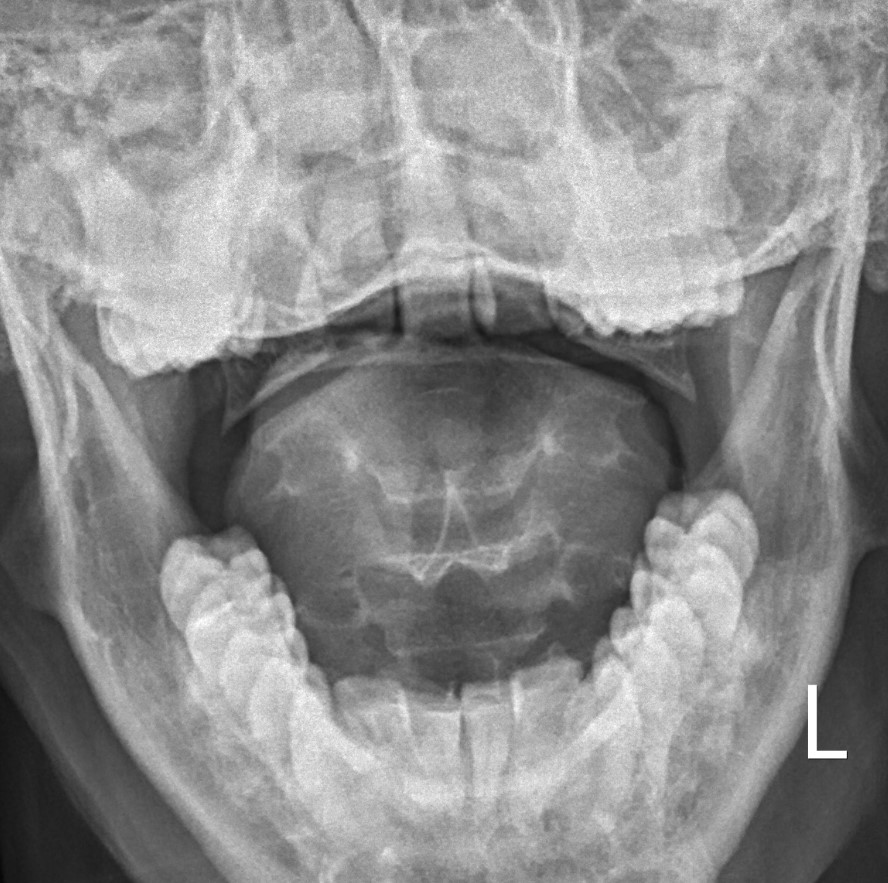

LMD

Lateral mass displacement

LMD 1LMD 2

Increased lateral mass displacement of 8 mm